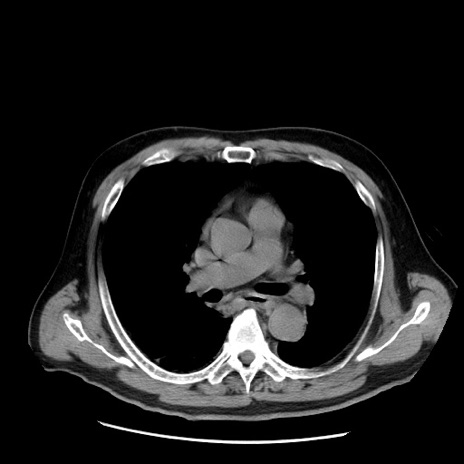

症例20(横断像)

【症例】 60歳代男性

【主訴】 腹部膨満、嘔吐

【現病歴】5日前頃より倦怠感を認め食事量減少し4日前の朝嘔吐、食事摂取困難となった。 3日前近医受診し点滴施行され整腸剤などを処方された。 当日他院を受診し、腹部膨満著明、炎症反応の上昇(CRP10.8、WBC11200)あり、紹介受診となる。

【身体所見】 意識JCS1 受け答えがはっきりしないBP 111/57mHg、 P 67bpm、、BT35.2°C、SpO2 97%(RA)、 腹部:膨隆、打診で鼓音あり、全体的に圧痛有り、腸蠕動音(-)、反跳痛ははっきりせず。

【データ】WBC 11400、CRP 14.20